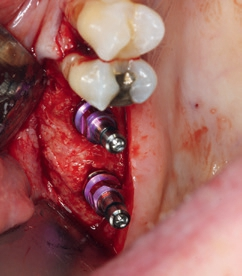

Nach einer komplikationslosen Einheilzeit von ca. 5 Monaten wurde mithilfe einer erneuten bildgebenden Diagnostik die Implantation geplant und in einem 2. Eingriff das Titangitter entfernt (Abb. 8). Die Kieferhöhle zeigte sich reizfrei bei einem nun ausreichenden horizontalen und vertikalen Knochenangebot für die Implantation in regio 16,17. In Lokalanästhesie wurde das Titangitter im Bereich der krestal angebrachten Sollbruchstelle in 2 Teile getrennt und entfernt (Abb. 9). Das darunterliegende Augmentat war sehr stabil und gut vaskularisiert und es konnte in regio 16 und 17 ein Implantatbett aufbereitet werden. In regio 17 wurde zudem ein kleiner interner Sinuslift durchgeführt. Die Achse wurde mit Positionierungshilfen parallel zu den Nachbarzähnen ausgerichtet und die Implantate konnten in idealer implantatprothetischer Ausrichtung primärstabil inseriert werden (Abb. 10 a und b). Es erfolgte ein erneuter primärer Wundverschluss und die Wundheilung verlief unauffällig.